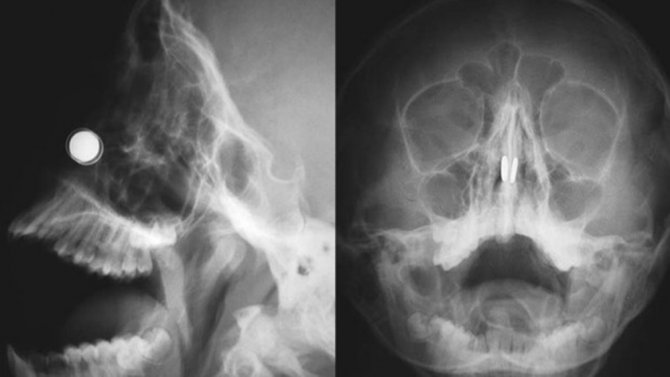

Konuyla ilgili açıklamalarda bulunan Yakın Doğu Üniversitesi Hastanesi'nde Doç. Dr. Kadir Çağdaş Kazıkdaş, en güçlü mıknatıslardan olan neodyum mıknatıslarının buruna girer girmez çocuğun burun direği etrafında birbirine yapıştığını açıkladı. Çocuğun mıknatısları burnuna soktuktan yaklaşık altı saat sonra dayanılmaz bir ağrı, burun kanaması ve burun içinde kabuklanma şikayetleri ile hastanenin acil servisine getirildiğini ifade eden Doç. Dr. Kazıkdaş, yapılan ilk müdahalede mıknatısların halen çocuğun burnunda olup olmadığının kesin olarak anlaşılamadığını, burun içerisinde de kanamaya bağlı çok fazla kabuklanma olduğunu, bu arada çocuğun duyduğu ağrı ve korku nedeniyle doktorların müdahale girişimlerini de engellediğini söyledi. Doç. Dr. Kazıkdaş daha sonra hastanın Kulak, Burun Boğaz Polikliniği'ne sevk edilerek, yüz röntgeninin çekildiğini, böylece burun içerisinde birbirine kenetlenmiş olan mıknatısların tespit edilebildiğini söyledi.

Geleneksel cerrahi aletlerle mıknatısları çıkarmayı denediklerini ama bu şekilde sonuç alamadıklarını ifade eden Doç. Dr. Kadir Çağdaş Kazıkdaş, son olarak burun içinde kenetlenmiş olan mıknatısları kaldırıp çıkarmak için burun dışından sıradan mıknatıslar kullanmayı düşündüklerini ifade ederek şöyle devam etti; "Bu yöntem ile sol taraftaki mıknatısı kolaylıkla çıkarmayı başardık. Ardından ikinci mıknatısı çıkarmak da saniyeler sürdü. Çocuğun burun kıkırdağında oluşan hasarlı bölgeye ve travmatize olan dokulara yapay yama uygulandı. İlerleyen dönemdeki iyileşmeyi desteklemesi için silikon burun ateli de takıldı. Atel operasyon sonrasında on gün boyunca hastanın burnunda takılı kaldı."